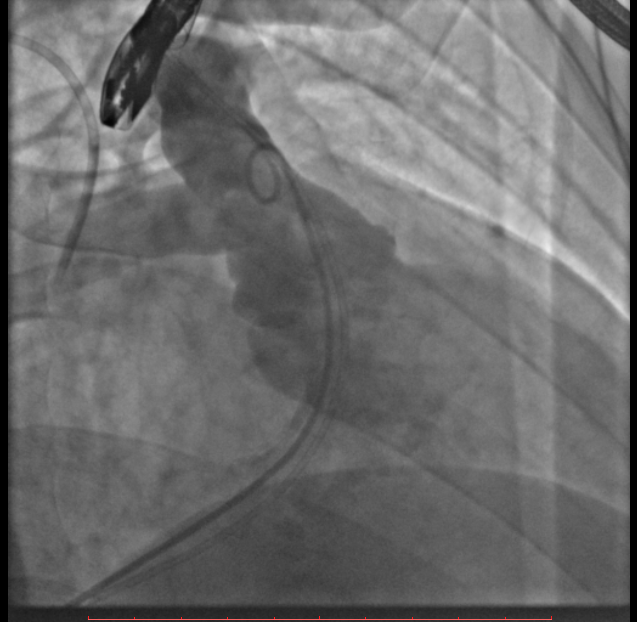

术中测量患者基础主动脉、肺动脉、右心室压力分别为111/58mmHg、31/4/13mmHg、34/1/6mmHg,通过肺动脉造影,术中测量球囊内径为32mm(见图二),选择36-25mm VENUS-P肺动脉瓣膜,在肺动脉造影指引下逐步打开瓣膜。考虑到患者肺动脉分叉较短,存在瓣膜释放后移位风险,故选择高位释放法(图三)。但释放瓣膜后造影提示右肺动脉开口局部被阻挡(图四),复测患者主肺动脉、左肺动脉、右肺动脉压力分别为57/13/25mmHg、55/12/24mmHg、27/7/14mmHg。

图二:术中扩张球囊刚好堵住右室流出道,测量球囊内经为32mm